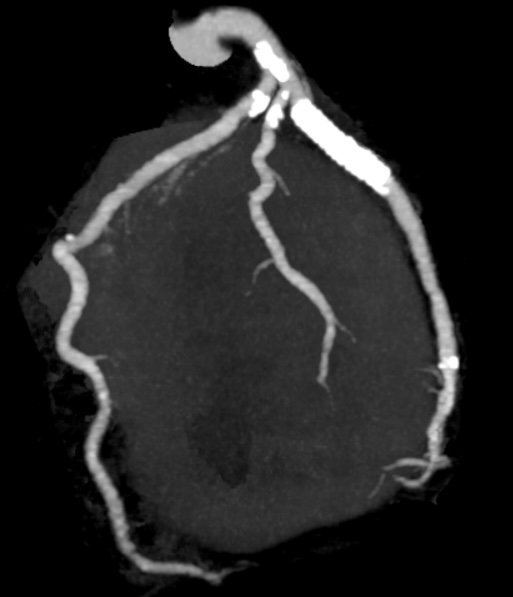

【冠動脈CT】

心臓を栄養する血管である冠動脈の走行や詰まっているところ、狭くなっているところがないかを調べる検査です。

主に狭心症や心筋梗塞などの診断や以前に狭心症の治療をした方の経過観察、また治療方針を決めるのに有用です。

心電図をとりながら造影剤を注入して息止めをして撮影をします。

最新の320列CTが導入されているため1回転(0.275秒)1心拍で心臓全体の撮影が可能です。

そのため息止めの時間が短く被曝も少ないですが、ブレが少なく精度の高い検査ができます。

撮影後には3D画像を作成し、色々な角度から観察することができるようになります。